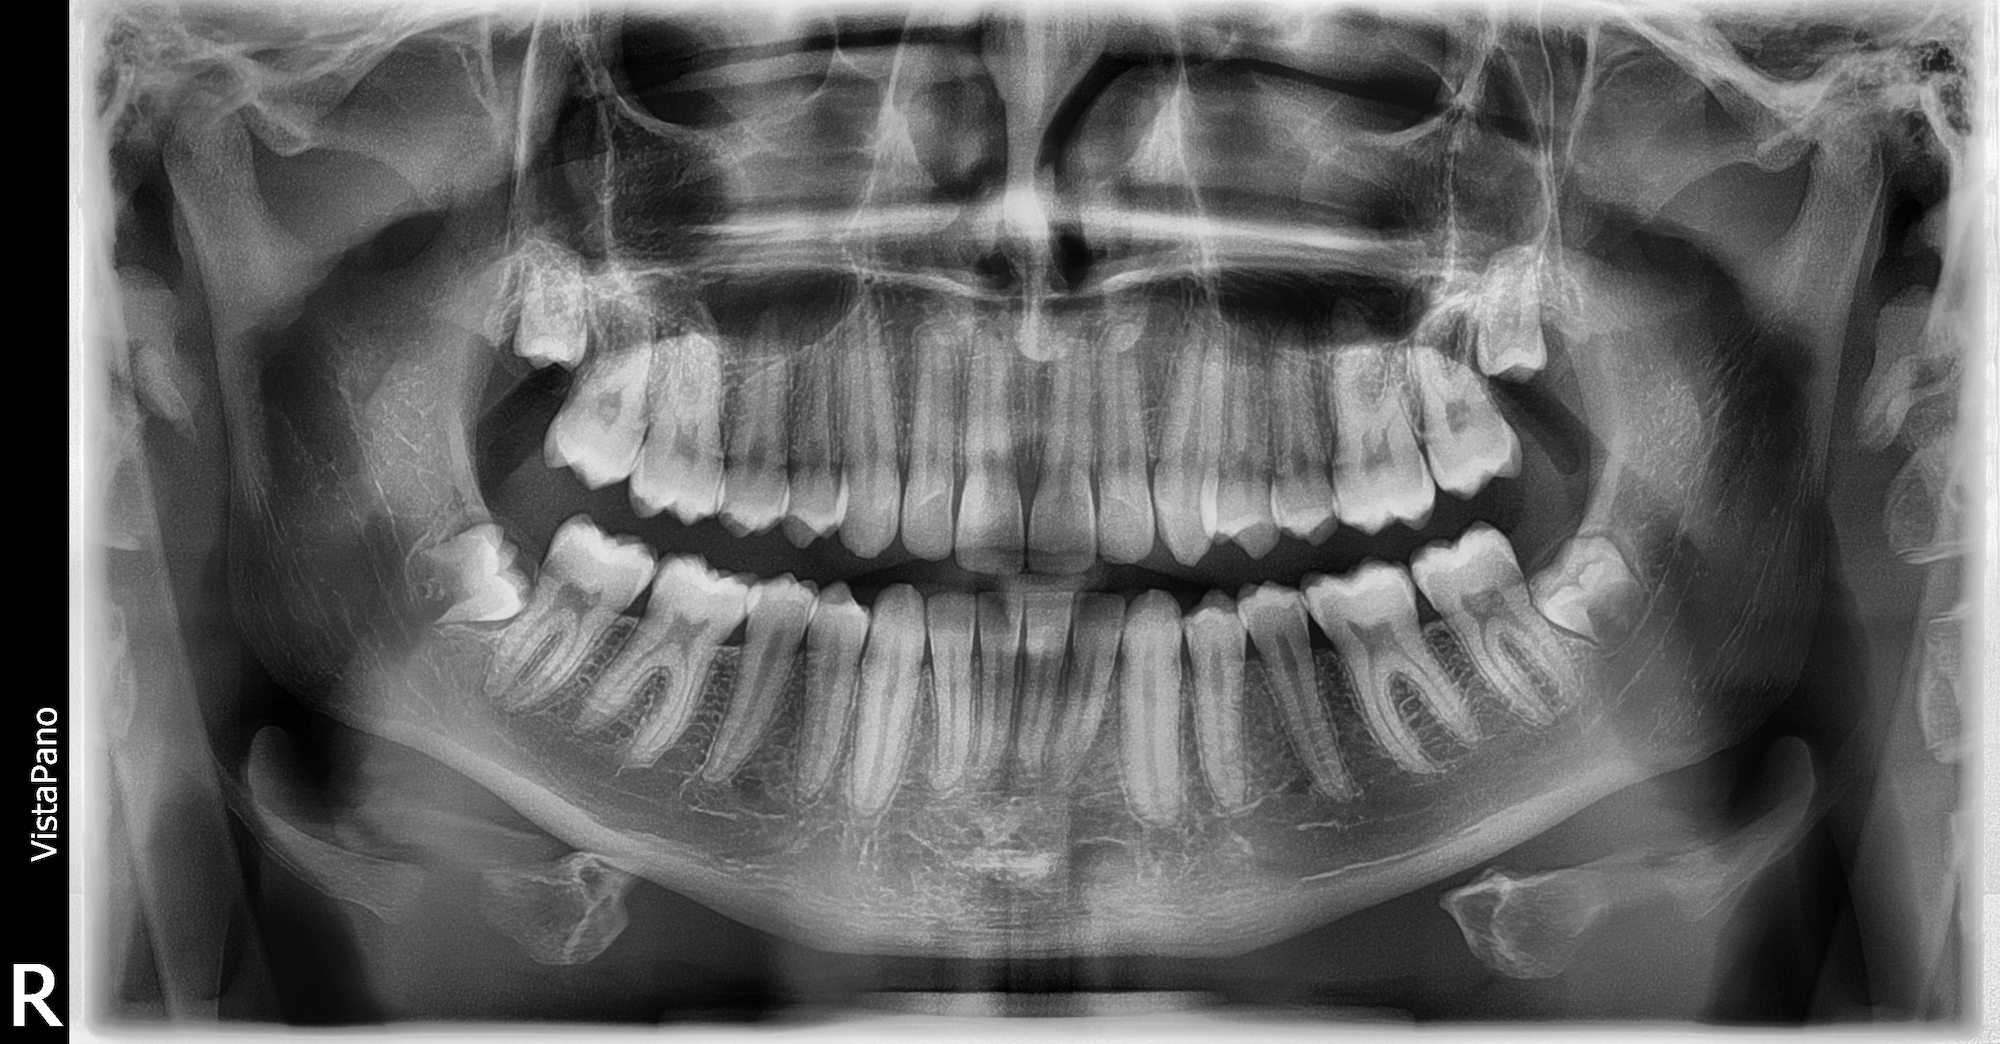

Dabei können grundsätzlich unterschiedliche Beweggründe dazu führen, sich einer operativen Behandlung zu unterziehen. Der am meisten vertretene Fall ist das Entfernen der Weisheitszähne. Gerade im jungen Erwachsenenalter wird individuell immer wieder zur Entfernung der letzten Zähne in der Zahnreihe geraten. Gründe dafür können Schmerzen oder der Platzmangel im Kiefer sein. Neben Weisheitszähnen können auch andere Probleme zu einem chirurgischen Eingriff führen. Dazu zählen neben der Implantologie  auch Wurzelspitzenresektionen, operativ notwendige Zahnentfernungen und die Behandlung von gutartigen Tumoren. In besonderen Fällen leiten wir Sie auch gern an unsere spezialisierten Kollegen weiter.

Leider können auch bereits behandelnde Zähne erneut Probleme bereiten. So auch ein schmerzender Zahn mit einer vorhandenen Wurzelkanalfüllung. Manchmal ist es durch eine sogenannte Wurzelspitzenresektion trotzdem möglich, die Zähne dennoch zu erhalten. Dabei wird meist unter örtlicher Betäubung die Entzündung, die meist um die Wurzelspitze herum sitzt, chirurgisch entfernt. Mithilfe einer Röntgenaufnahme wird die Operation dann im Nachgang überprüft.